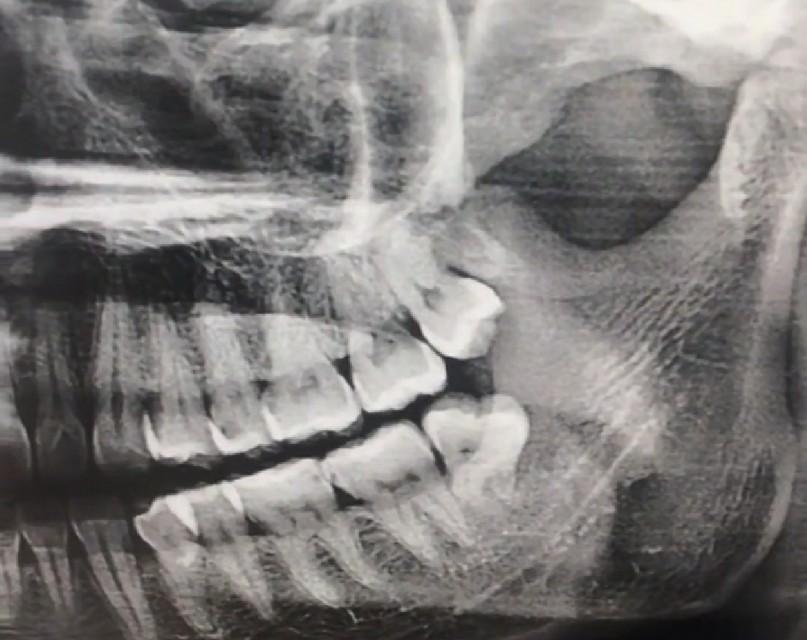

下顎的智齒拔起來可以說相當(dāng)?shù)睦щy,它有逆生長的、壓根不露頭的、還有牙根帶鉤的、關(guān)鍵是下顎接近腦神經(jīng),拔下額的智齒必須要拍牙齒圖片,拍一個圖片也就50塊錢左右,如果圖片出來智齒的位置比較麻煩,好還是多花點(diǎn)錢去三甲醫(yī)院拔除,下顎智齒拔除的困難度不同價格也不同,有的隱藏智齒需要開刀縫合切割,長時間甚至需要醫(yī)生一個多小時的折騰,三甲醫(yī)院的價格從800到2000也就不奇怪了。